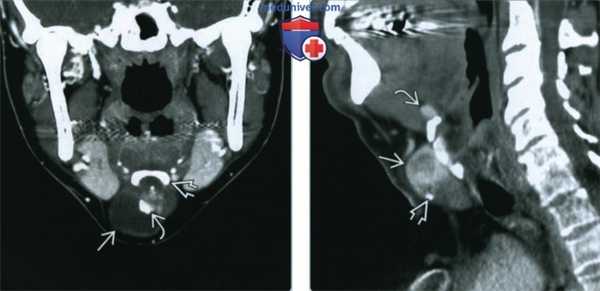

(Слева) На аксиальном рисунке изображена язычная щитовидная железа в задних отделах языка по средней линии, непосредственно глубже слепого отверстия. Четкие контуры и срединное расположение в области дна полости рта или в основании языка - типичные признаки язычной щитовидной железы.

(Справа) На аксиальной КТ с КУ в основании языка по средней линии определяется округлое контрастирующееся образование с четкими контурами, с минимальной деформацией подбородочно-язычных мышц. Плотность язычной щитовидной железы намного выше по сравнению с минимально контрастирующейся язычной миндалиной. (Слева) На аксиальной КТ с КУ в области дна по средней линии определяется объемное образование с четкими контурами, представленное эктопической тканью щитовидной железы неоднородной плотности (может быть сопоставимо с ранними изменениями при зобе).